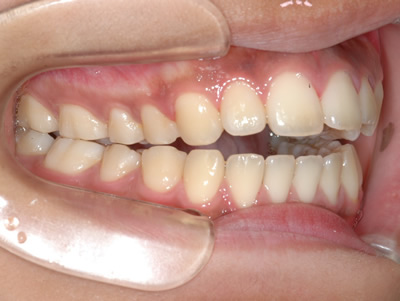

上顎前歯のガタガタと前歯の反対咬合を気にして来院されました。上下顎の左右第一小臼歯 (4番目の歯) を抜歯し、マルチブラケット装置で治療しました。治療期間は2年10ヶ月かかりました。

初診時

終了時